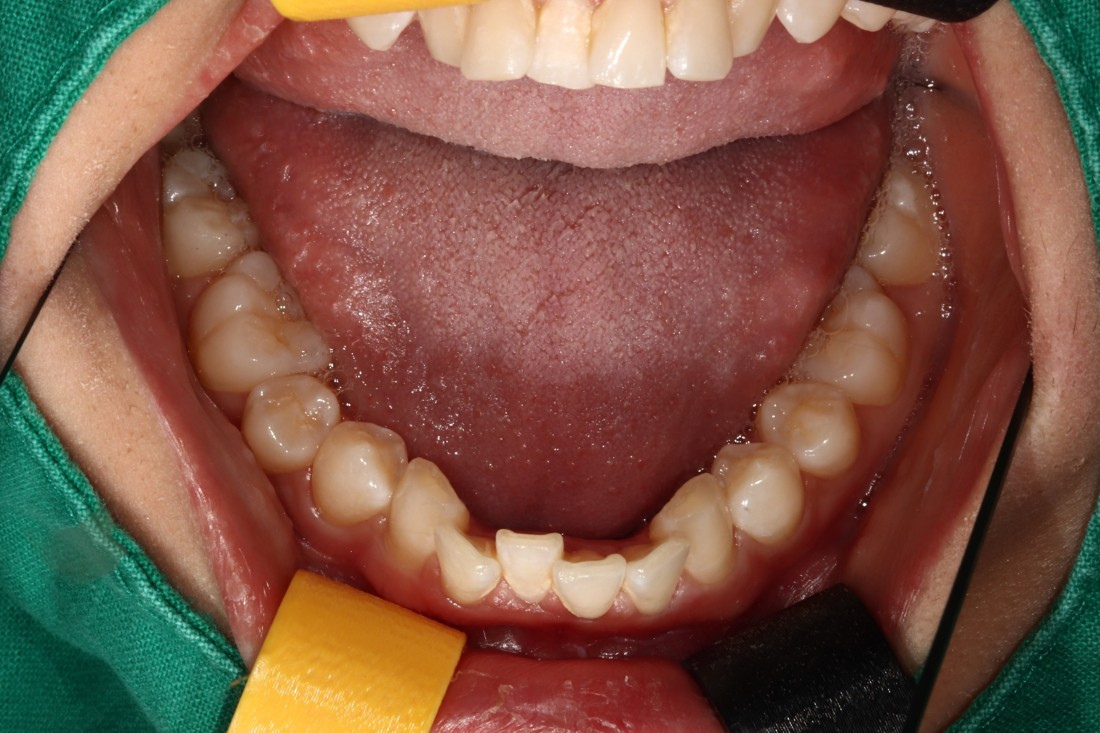

광주 교정치과

충치치료 + 치아교정 동시 케이스

광주 교정치과 추천하는 이유는

전문의 충치치료까지 동시에 가능하여

토탈 구강건강 관리를 받으실 수 있기 때문입니다.